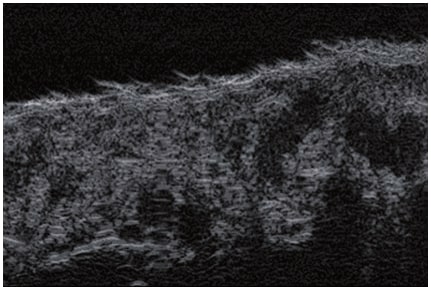

La ecografía Doppler permite obtener imágenes de grandes vasos y perforantes que suelen estar situados en las capas más profundas del tejido subcutáneo (fig. 1). Desgraciadamente, la ecografía convencional no es capaz de obtener imágenes de vasos más pequeños. Para visualizar los vasos más pequeños situados cerca de la superficie de la epidermis y en la capa superior del tejido subcutáneo, se utiliza el HFU (fig. 1). Gracias al uso de transductores con frecuencias superiores a 20 MHz, se obtiene una imagen ecográfica de alta resolución en la que podemos diferenciar estructuras menores de 0,1 mm. Sin embargo, cuanto mayor es la resolución, menor es la penetración del haz de ultrasonidos en las capas de la piel. Por lo tanto, dependiendo del transductor y del aparato, es posible penetrar en la piel hasta una profundidad de 20-30 mm como máximo. Tal penetración, junto con la alta resolución de la imagen, permite la evaluación incluso de vasos sanguíneos muy pequeños (fig. 2). Durante el examen con el uso de transductores de alta frecuencia, se puede evaluar con precisión el curso y la ubicación de los pequeños vasos en la piel. Esto es particularmente relevante para la selección del método de cierre del vaso y la planificación del procedimiento ya que, en la práctica, la superficie de la piel muestra muy a menudo únicamente un pequeño número de vasos o un ligero fragmento de un vaso; solo tras el examen por ecografía podemos determinar su número y curso reales. Para un cierre eficaz del vaso, es necesario hacerlo en toda su longitud. No debe limitarse al fragmento visto «a simple vista» en la superficie de la piel, ya que el cierre del fragmento causará su rápida recanalización(7). Con frecuencia, el vaso visible en la superficie de la piel cambia su curso, se vuelve más tortuoso y se desplaza a las capas más profundas de la piel(8). Por lo tanto, el curso de la vena y las perforantes deben conocerse y determinarse bien antes del procedimiento. El HFU también permite obtener imágenes de las perforantes entre pequeños vasos. Además, aparte de la evaluación del curso y la anatomía, la imagen ecográfica, gracias al software de ultrasonidos, también permite determinar los parámetros básicos como el diámetro del vaso, el grosor de su pared, la profundidad en la piel así como la presencia o ausencia de perfusión en el interior del vaso(6) (fig. 3). Gracias al transductor electrónico multielemento con la frecuencia de 40 MHz introducido en el mercado por Ultrasonix, también es posible visualizar la perfusión en los vasos en el modo Doppler color (fig. 4).